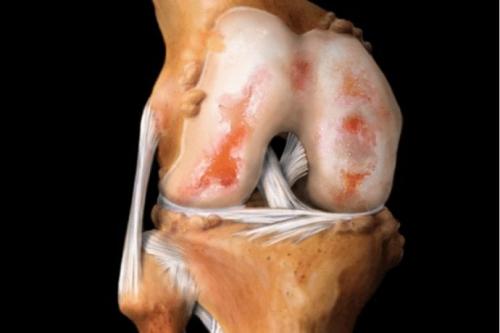

Вид на поражённую хрящевую поверхность.

Так выглядит разрушенный хрящ.